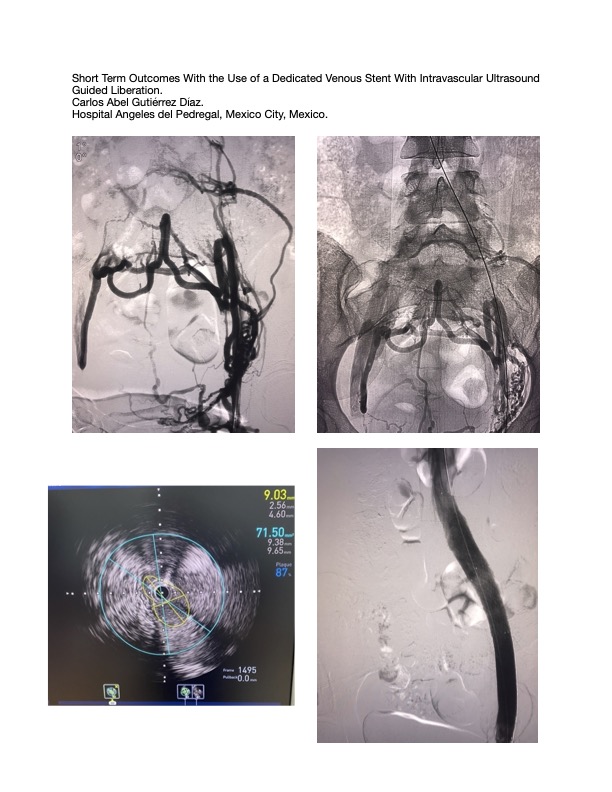

Short Term Outcomes With the Use of a Dedicated Venous Stent With Intravascular Ultrasound Guided Liberation

Iliac vein stenting is the treatment of choice for patients with posthrombotic syndrome and iliac vein compression. The new dedicated venous stents provide higher diameters and larger lengths with precise deployment and stronger radial force, ideal characteristics for the treatment of these fibrotic and restrictive lesions. The intravascular ultrasound (IVUS) is a fundamental device to measure de proper stent diameter, length and to identify the proximal and distal landing zones. The use of intravascular ultrasound increases accuracy and is associated with improved outcomes and reduced complications. Furthermore, intravascular ultrasound (IVUS) helps in identifying significant lesions that are ambiguous by venography and reducing treatment of lesions that are proven insignificant. Additionally, several patients may have undiagnosed and/or underrecognized anatomic obstruction (May-Thurner syndrome). The venous stenting is indicated for symptomatic patients with lower extremity swelling and cutaneous changes.

Patients with obstructive disease of the common iliac, external iliac and femoral veins and a Clinical, Etiological, Anatomical, Pathophysiological class of 3 or higher or a Venous Clinical Severity Score of 2 or greater were enrolled in this retrospective, single center, single arm study in Mexico City. Patients with posthrombotic syndrome and iliac vein compression were included. Symptomatic venous reflux was measured with duplex ultrasound (greater than 1 second in the deep venous system) and lesion anatomy was assessed with CT scan. The patients were followed up for 12 months after the index procedure for the assessment of patency and safety.

Between January 2022 and August 2025 a total of 50 patients were treated with a dedicated venous stent (Venovo, BD). The mean age was 59.2 years and 80% were women and 20% were men. Twenty patients with non thrombotic lesions and 30 patients with postrombotic lesions. The stent was measured with standard IVUS technique using 16mm Venovo stent for the common iliac vein, 14mm for the external iliac vein and 12mm for the common femoral vein. The overall 12-month primary patency rate was 88% (44/50), and the 12-month primary patency rate was 94.8% (19/20) for the nonthrombotic group and 80% (25/30) for the postthrombotic group. Following treatment all patients improve the CEAP and VCSS score.

The results of this study demonstrated good short term patency using a dedicated venous stent for iliofemoral obstruction. Iliac vein stenting with the Venovo (BD) venous stent is very effective with symptom improvement in the majority of patients. The endovascular approach is now a widely accepted standard. The utilization of intravascular ultrasound (IVUS) during venous stent placement was associated with better results and proper measures providing adequate stent inflow and outflow, factors the improve patency.